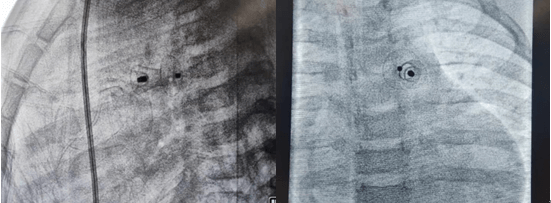

2021年11月12日,延安大學(xué)咸陽醫(yī)院心血管病院吳棟梁院長、李陽主任介入團(tuán)隊(duì)為一例年僅13個(gè)月的女性患兒進(jìn)行了先天性心臟病動(dòng)脈導(dǎo)管未閉介入封堵手術(shù)。這是我院迄今為止介入封堵治療年齡最小、體重最輕的患兒,手術(shù)過程順利,封堵成功,解決了一家人的痛苦,患兒術(shù)后恢復(fù)良好,于2021年11月17日順利出院。

先天性心臟病發(fā)病率已逐年下降,但因我國人群基數(shù)大,所以患者并不少見,先天性心臟病也是心血管疾病中為數(shù)不多的可通過介入或者外科手術(shù)得到根治的疾病之一,一般手術(shù)多建議在3歲以后進(jìn)行,3歲以內(nèi)患兒因體重太小,對(duì)患兒進(jìn)行動(dòng)靜脈穿刺置管、手術(shù)操作過程及麻醉難度明顯增加。該患兒體重僅10kg,身高僅70cm多一點(diǎn),因動(dòng)脈導(dǎo)管分流量較大,影響患兒發(fā)育,反復(fù)因肺部感染誘發(fā)心衰,并已經(jīng)出現(xiàn)左房左室擴(kuò)大,需盡早手術(shù),否則出現(xiàn)心衰加重可能錯(cuò)過手術(shù)時(shí)機(jī),但患兒家屬對(duì)外科開胸心存畏懼,而且外科手術(shù)后胸部手術(shù)瘢痕明顯影響女性患者的美觀,通過多方打聽,患兒聯(lián)系到了何克強(qiáng)醫(yī)生、李陽主任及吳棟梁院長手術(shù)團(tuán)隊(duì),家屬對(duì)醫(yī)生期望值極高,因患兒情況特殊,吳棟梁院長及心血管內(nèi)科五病區(qū)團(tuán)隊(duì)術(shù)前對(duì)患兒手術(shù)情況進(jìn)行討論,制定嚴(yán)密的手術(shù)方案,對(duì)手術(shù)中可能出現(xiàn)的難點(diǎn)進(jìn)行充分的準(zhǔn)備,最終在穿刺及麻醉成功后1小時(shí)內(nèi)便順利完成手術(shù),此例手術(shù)的開展,標(biāo)志著我院在先心病介入治療方面再上新臺(tái)階,患兒術(shù)后恢復(fù)非常好,得到了患兒家屬的肯定,解決了患兒一家的困擾。